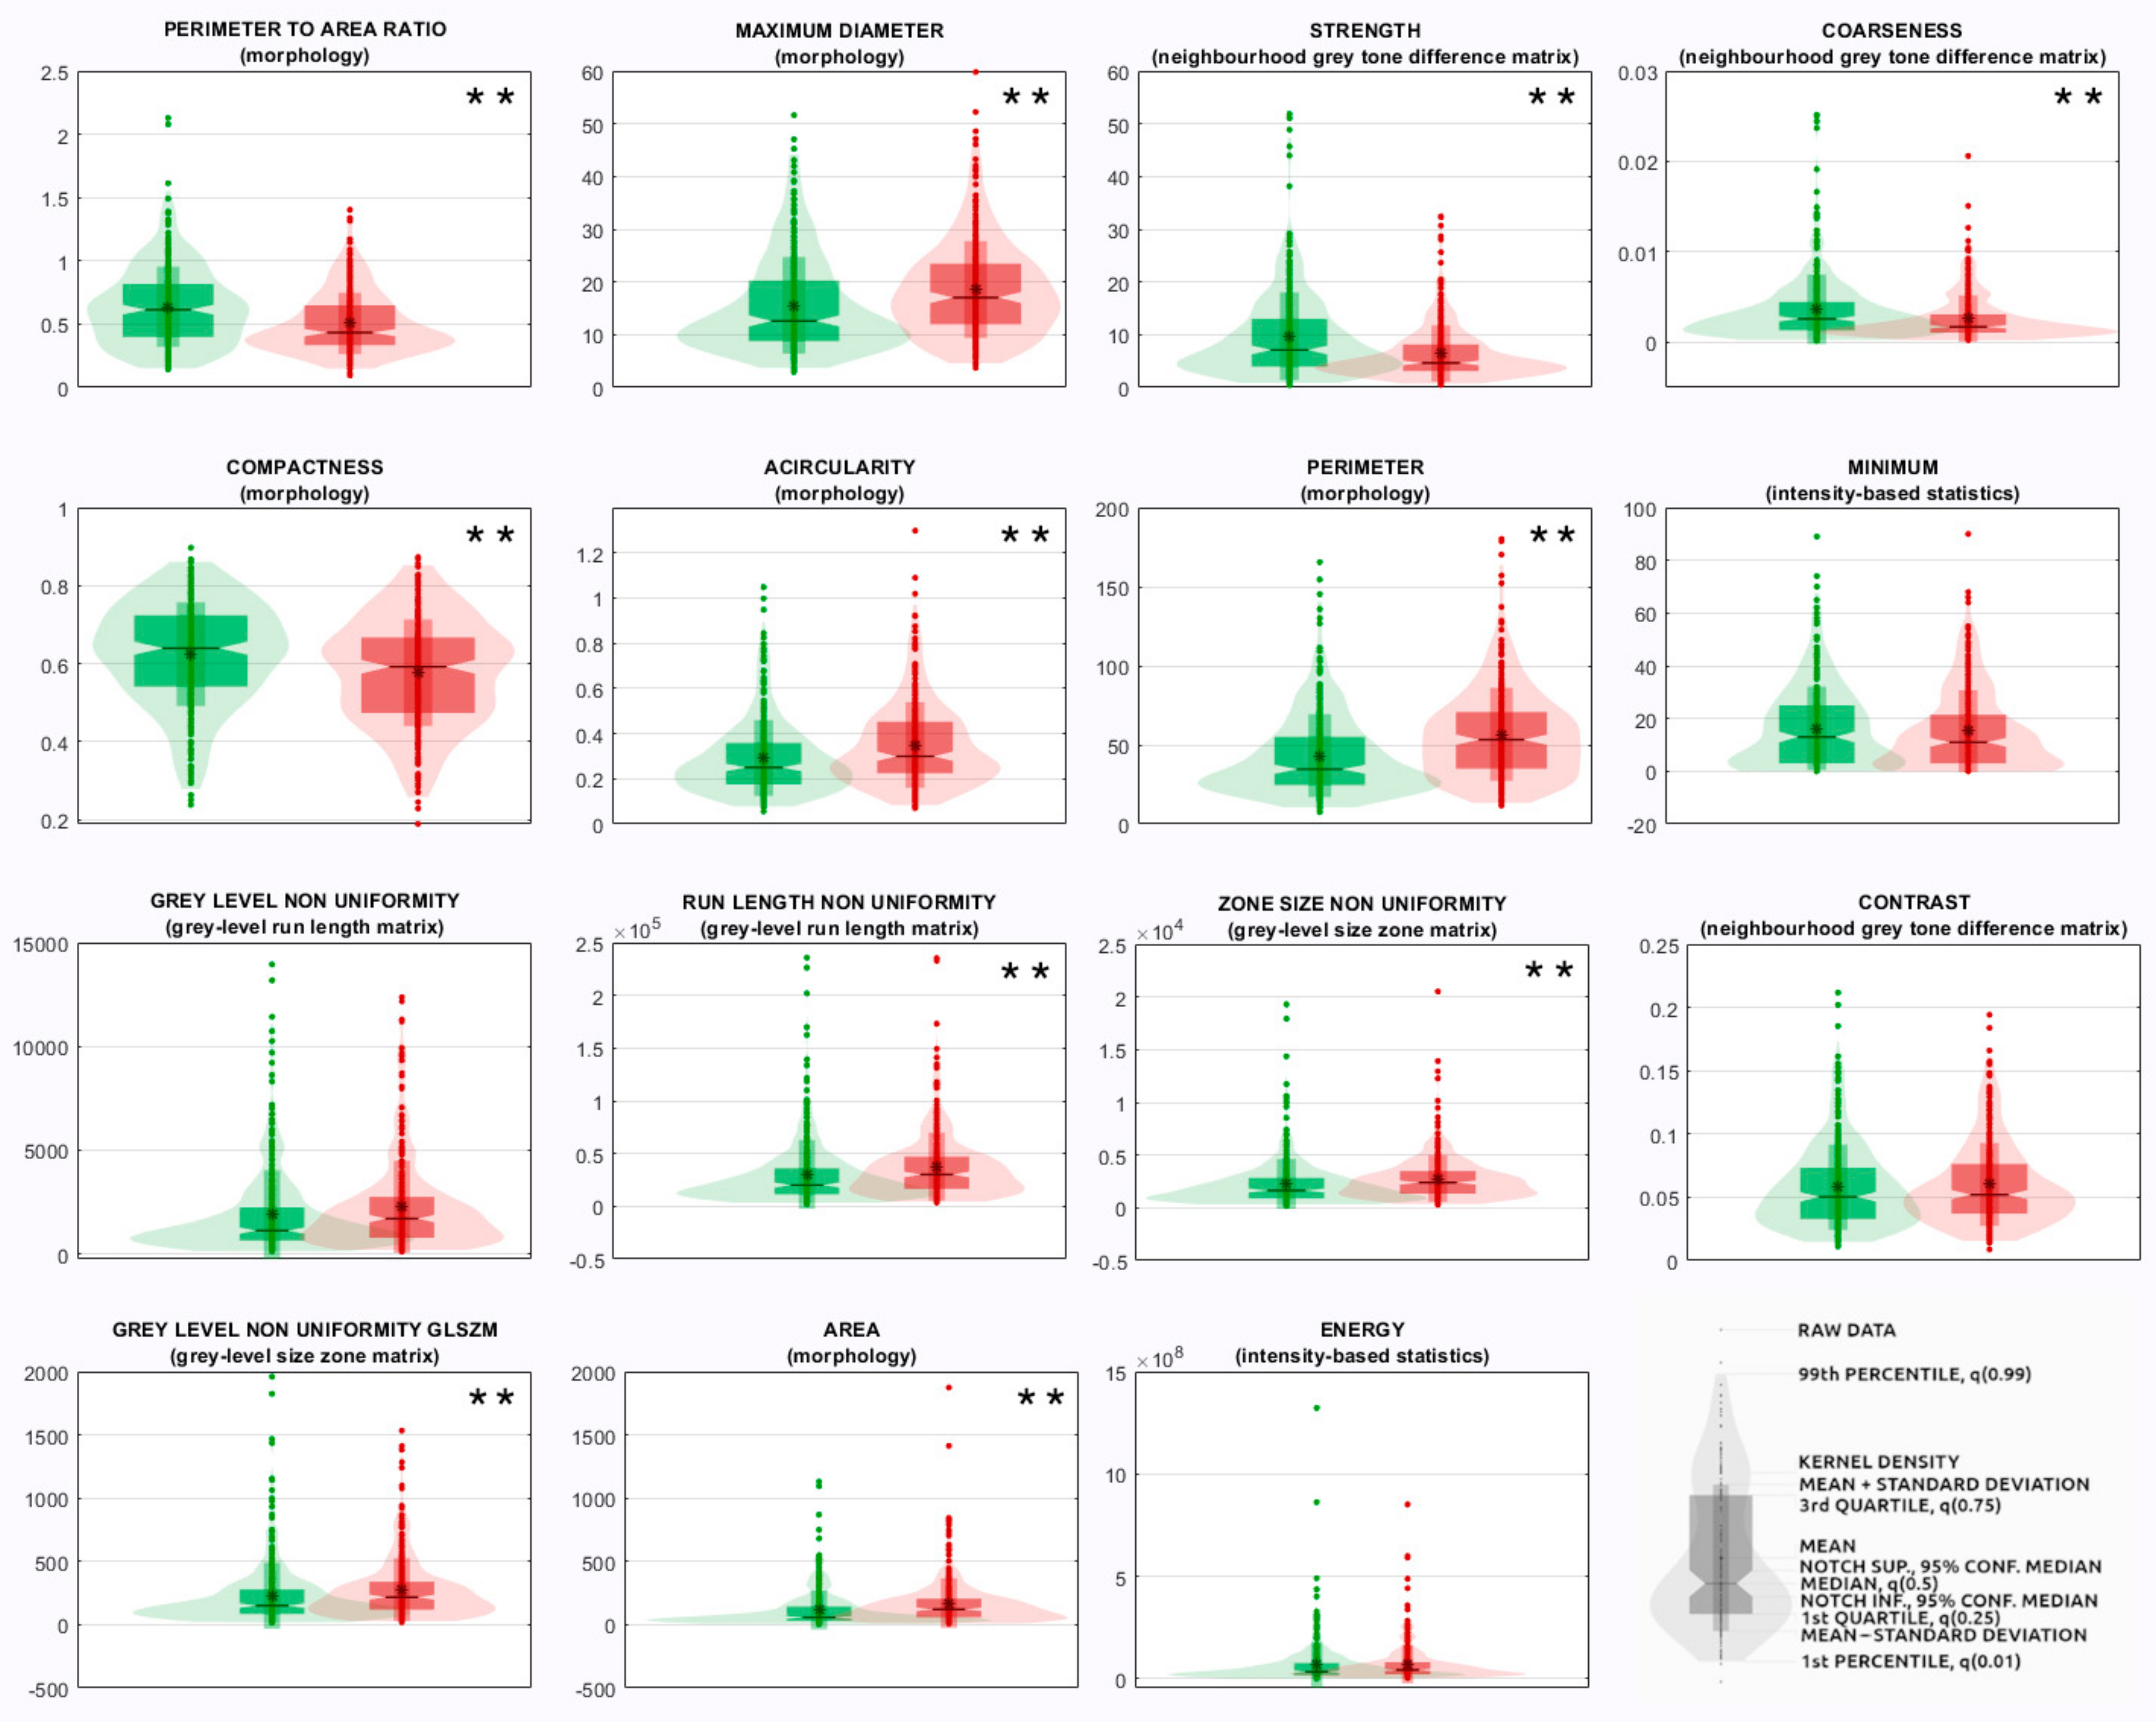

- The radiomics features measured from the segmented ROI were 107 quantitative descriptors and belonged to different families: morphology, intensity-based statistics, intensity histogram, grey-level co-occurrence matrix (GLCM), grey-level run length matrix (GLRLM), grey-level size zone matrix (GLSZM), neighborhood grey tone difference matrix (NGTDM), grey-level distance zone matrix (GLDZM), and neighboring grey-level dependence matrix (NGLDM). Their definition, computation, and nomenclature are compliant with the IBSI guidelines, except for the features of the family morphology, originally designed for 3D images, which were replaced with ten 2D equivalent features (e.g., 3D features volume and surface were replaced with 2D features area and perimeter, respectively). Radiomic features were selected as those showing an intraclass correlation coefficient >0.75 among the two intra-observer and inter-observer segmentations on the random subsample of images described in point (1), since according to the 95% confidence interval of the intraclass correlation coefficient estimate, values lower than 0.5, between 0.5 and 0.75, between 0.75 and 0.9, and higher than 0.9 are indicative of poor, moderate, good, and excellent reliability, respectively [14]. Steps from (2) to (3) were performed using the TRACE4 Radiomics tool. Radiomic features were reported by TRACE4 according to IBSI standards.

2.4. Statistical Analysis

3.2. Radiomic-Based Machine Learning Modelling

| Rank | Feature Family | Feature Name |

|---|---|---|

| 1 | Morphology | Perimeter-to-area ratio ** |

| 2 | Morphology | Maximum diameter ** |

| 3 | Morphology | Compactness ** |

| 4 | Morphology | Acircularity ** |

| 5 | Morphology | Perimeter ** |

| 6 | Morphology | Area ** |

| 7 | Morphology | Center of mass shift ** |

| 8 | Morphology | Circularity * |

| 9 | Neighborhood grey tone difference matrix | Strength ** |

| 10 | Neighborhood grey tone difference matrix | Coarseness ** |

| 11 | Neighborhood grey tone difference matrix | Contrast |

| 12 | Neighborhood grey tone difference matrix | Busyness * |

| 13 | Grey-level size zone matrix | Zone size non-uniformity ** |

| 14 | Grey-level size zone matrix | Grey-level non-uniformity glszm ** |

| 15 | Neighboring grey-level dependence matrix | Dependence count non-uniformity ** |

| 16 | Neighboring grey-level dependence matrix | Low-dependence low-grey-level emphasis |

| 17 | Grey-level run length matrix | Grey-level non-uniformity |

| 18 | Grey-level run length matrix | Run length non-uniformity |

| 19 | Intensity-based statistics | Minimum |

| 20 | Intensity-based statistics | Energy |

| 21 | Intensity-based statistics | Variance |

| 22 | Intensity-based statistics | Quartile coefficient |

| 23 | Intensity-based statistics | 10th percentile |

| 24 | Intensity histogram | 10th percentile |

| 25 | Grey-level co-occurrence matrix | First measure of information correlation |